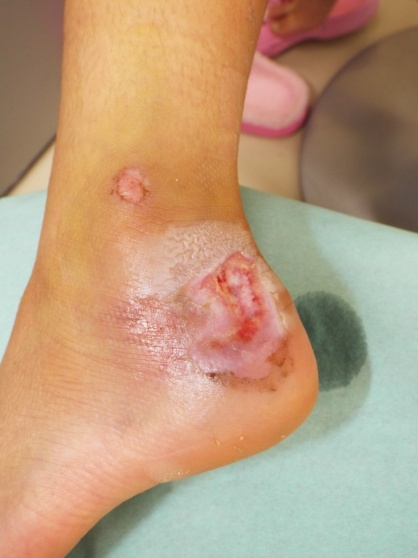

8歳の女のコ、2019年4月20日父親の自転車の後部座席に乗車中に受傷しました。

直ぐに救急病院を受診してレントゲンに異常がないと言われ帰宅しましたが、腫れと痛みが続くため二日後の4月22日受診されました。創部は乾燥して一部黒色調に変化し、周囲には感染を示す赤みがありました。

受傷10日目には黒色の壊死組織がとれ皮膚潰瘍の状態になりました。周囲の浅い部分は上皮化してきました。

受傷1か月目の状態です。徐々に潰瘍部が縮小してきました。